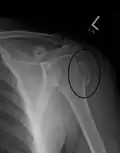

Proximal

Proximal humerus fractures most often occur among elderly people with osteoporosis who fall on an outstretched arm.[9] Less frequently, proximal fractures occur from motor vehicle accidents, gunshots, and violent muscle contractions from an electric shock or seizure.[10][5] Other risk factors for proximal fractures include having a low bone mineral density, having impaired vision and balance, and tobacco smoking.[11] A stress fracture of the proximal and shaft regions can occur after an excessive amount of throwing, such as pitching in baseball.[6]

Definitive diagnosis of humerus fractures is typically made through radiographic imaging. For proximal fractures, X-rays can be taken from a scapular anteroposterior (AP) view, which takes an image of the front of the shoulder region from an angle, a scapular Y view, which takes an image of the back of the shoulder region from an angle, and an axillar lateral view, which has the patient lie on his or her back, lift the bottom half of the arm up to the side, and have an image taken of the axilla region underneath the shoulder.[9] Fractures of the humerus shaft are usually correctly identified with radiographic images taken from the AP and lateral viewpoints.[12] Damage to the radial nerve from a shaft fracture can be identified by an inability to bend the hand backwards or by decreased sensation in the back of the hand.[5] Images of the distal region are often of poor quality due to the patient being unable to extend the elbow because of pain. If a severe distal fracture is suspected, then a computed tomography (CT) scan can provide greater detail of the fracture. Nondisplaced distal fractures may not be directly visible; they may only be visible due to fat being displaced because of internal bleeding in the elbow.[7]

Fractures of the humerus are classified based on the location of the fracture and then by the type of fracture. There are three locations that humerus fractures occur: at the proximal location, which is the top of the humerus near the shoulder, in the middle, which is at the shaft of the humerus, and the distal location, which is the bottom of the humerus near the elbow.[9] Proximal fractures are classified into one of four types of fractures based on the displacement of the greater tubercle, the lesser tubercle, the surgical neck, and the anatomical neck, which are the four parts of the proximal humerus, with fracture displacement being defined as at least one centimeter of separation or an angulation greater than 45 degrees. One-part fractures involve no displacement of any parts of the humerus, two-part fractures have one part displaced relative to the other three; three-part fractures have two displaced fragments, and four-part fractures have all fragments displaced from each other.[13][14][3] Fractures of the humerus shaft are subdivided into transverse fractures, spiral fractures, "butterfly" fractures, which are a combination of transverse and spiral fractures, and pathological fractures, which are fractures caused by medical conditions.[12] Distal fractures are split between supracondylar fractures, which are transverse fractures above the two condyles at the bottom of the humerus, and intercondylar fractures, which involve a T- or Y-shaped fracture that splits the condyles.[7]